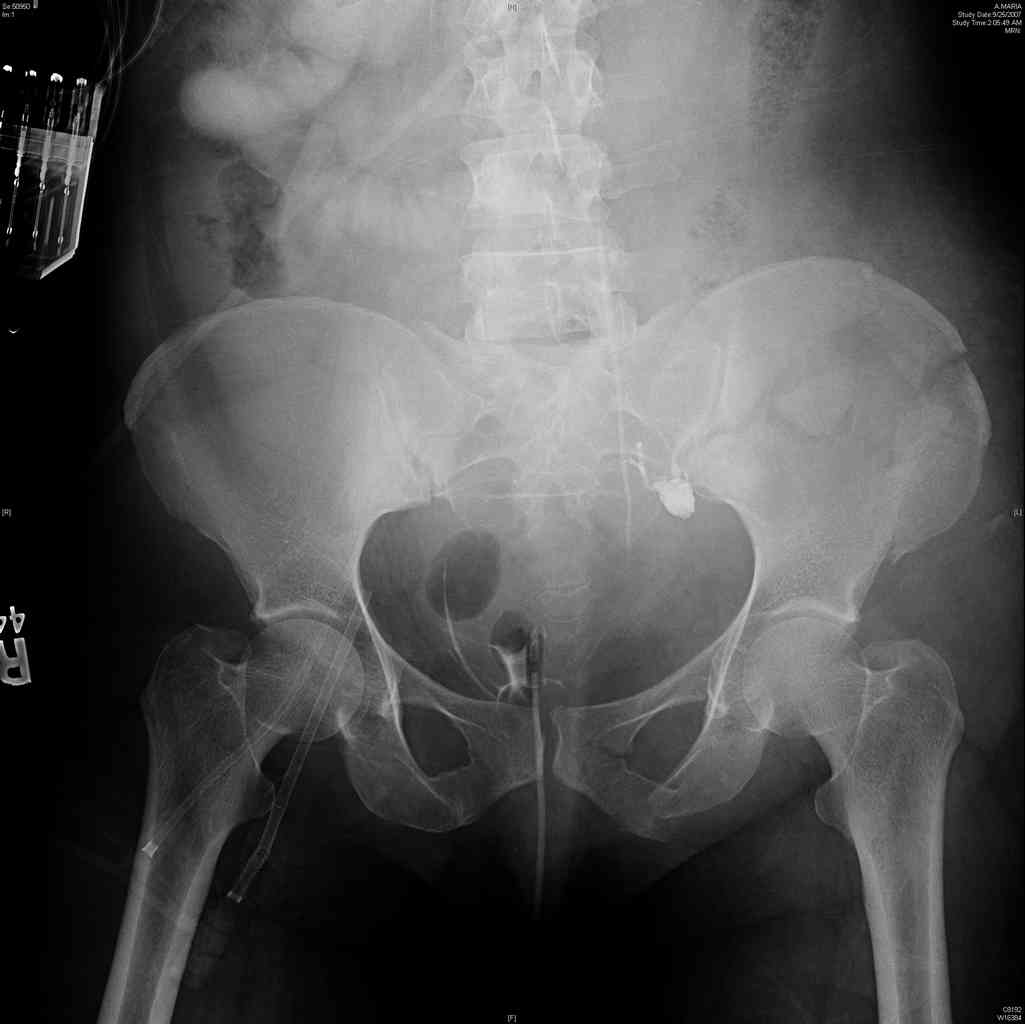

comminuted crescent fx

40 ish female ejected from car. Unstable, DPL negative, went to angio and had her pelvic bleeds embolized after many units of blood. GCS 6, floating elbow, clavicle, bothbones, etc.

My standard approach to this pelvis would be posterior, reduce/lag/plate thecrest, reduce/plate the caudal extent on the posterior crest and 1-2 lags back to front. In this case, the crest comminution seems to make plating all the way to the ASIS useless, as the plate would be on free floating fragments. Would plating the posterior extent of the fracture to secure the reduction at the SI joint and 2 screws back to front be sufficient fixation? Would anyone do a perc reduction and perc back to front screws, and would that be sufficient if the SI joint could be reduced (although I don't see how this could be accurately reduced closed). Would an ilioninguinal with a pelvic brim plate and posterior column screws be a better approach, although reducing the SI would be more indirect and less accurate?